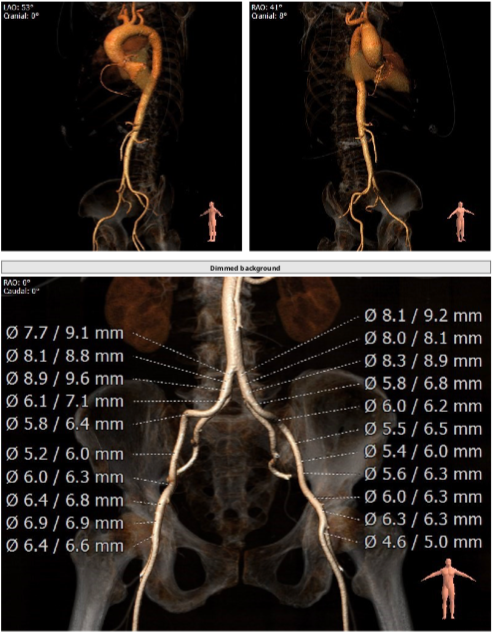

该病例为70岁女性患者,间歇胸闷气短17年,反复住院药物保守治疗,效果不佳,10日前症状加重,伴有胸痛、头晕、黑朦,双下肢水肿,转于我院就诊。经检查分析,诊断为重度主动脉瓣狭窄,风心病,患者主动脉瓣叶增厚,左心耳血栓,左冠开口小于10mm,存在一定冠脉阻塞风险,右侧股动脉分叉在股骨头中点,左侧股动脉分叉高于股骨头中点,双侧髂外动脉最小直径小于5.5mm,主动脉弓角偏大,对血管介入造成难点,同时易引起血管并发症,手术难度大。经杨毅宁教授团队充分评估,对患者采取全麻下经食道超声监测,选用目前行业最低入路要求美敦力递送系统配合自带内联鞘进行介入。

根据术前CT分析,结合患者瓣膜钙化情况,决定预装Evolut PRO 26mm瓣膜,采用超声引导下穿刺,确保入路精准,对血管损伤最小。